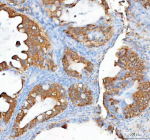

Immunohistochemical staining of RHOT2 using anti-RHOT2 antibody. RHOT2 was detected in a paraffin-embedded section of human prostate cancer tissue. Heat mediated antigen retrieval was performed in EDTA buffer (pH 8.0, epitope retrieval solution). The tissue section was blocked with 10% goat serum. The tissue section was then incubated with 2 ug/ml rabbit anti-RHOT2 antibody overnight at 4oC. Peroxidase Conjugated Goat Anti-rabbit IgG was used as secondary antibody and incubated for 30 minutes at 37oC. The tissue section was developed using an HRP secondary and DAB substrate.